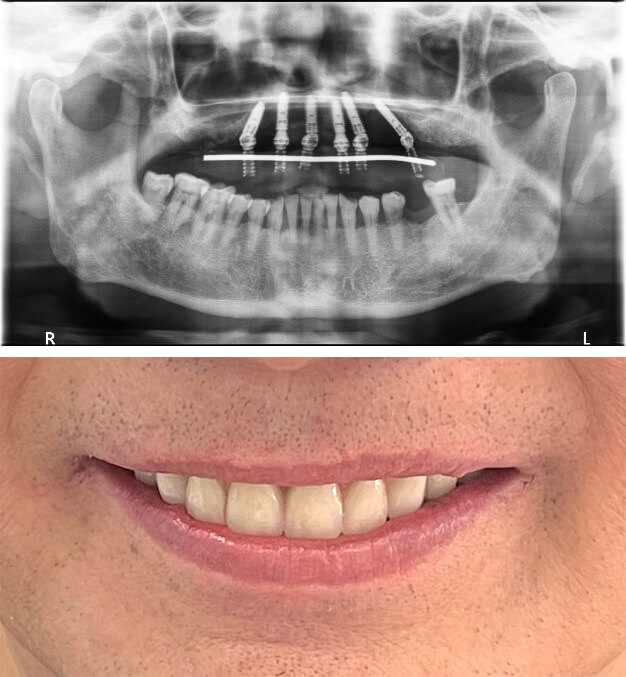

4 根植體

20240815vs 7 4根植體2

● 口腔狀況:上顎無牙

● 治療時間:當天有牙

● 植體數量:4 根

● 假牙類型:上顎、整座固定假牙